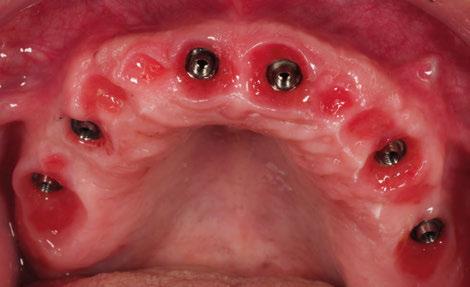

A los 4 meses, se retiró la prótesis provisional, verificando la